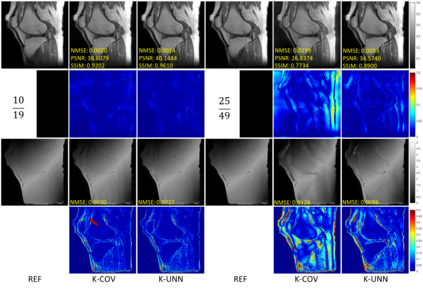

Recently, untrained neural networks (UNNs) have shown satisfactory performances for MR image reconstruction on random sampling trajectories without using additional full-sampled training data. However, the existing UNN-based approach does not fully use the MR image physical priors, resulting in poor performance in some common scenarios (e.g., partial Fourier, regular sampling, etc.) and the lack of theoretical guarantees for reconstruction accuracy. To bridge this gap, we propose a safeguarded k-space interpolation method for MRI using a specially designed UNN with a tripled architecture driven by three physical priors of the MR images (or k-space data), including sparsity, coil sensitivity smoothness, and phase smoothness. We also prove that the proposed method guarantees tight bounds for interpolated k-space data accuracy. Finally, ablation experiments show that the proposed method can more accurately characterize the physical priors of MR images than existing traditional methods. Additionally, under a series of commonly used sampling trajectories, experiments also show that the proposed method consistently outperforms traditional parallel imaging methods and existing UNNs, and even outperforms the state-of-the-art supervised-trained k-space deep learning methods in some cases.